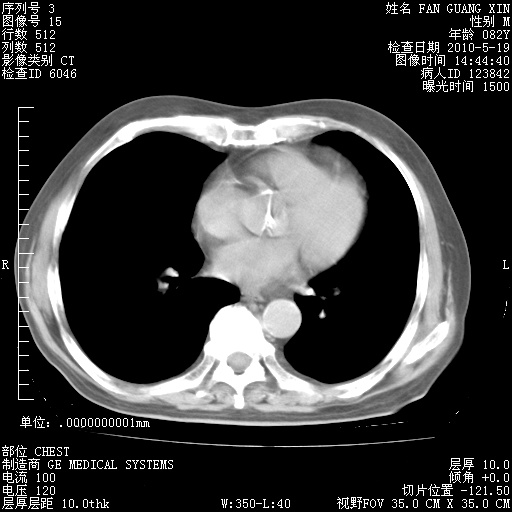

可改为口服强的松40-50mg/d治疗,若病情仍稳定,胸部阴影不再吸收可逐渐减量